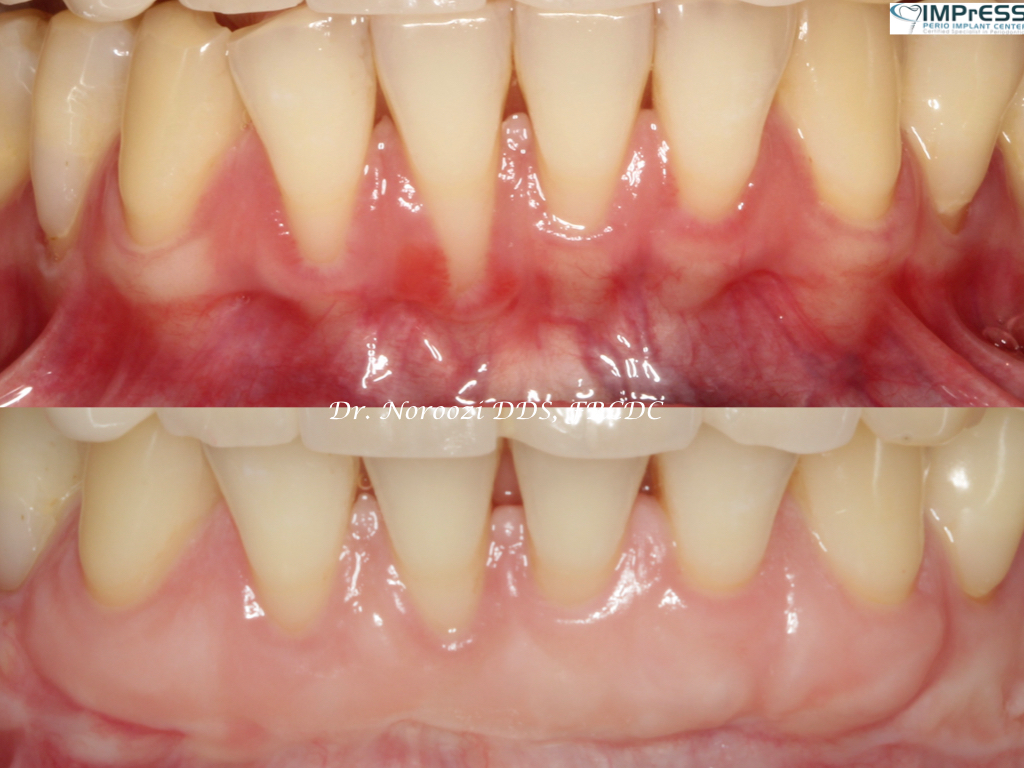

Connective Tissue Gingival Grafting for Gingival Recession